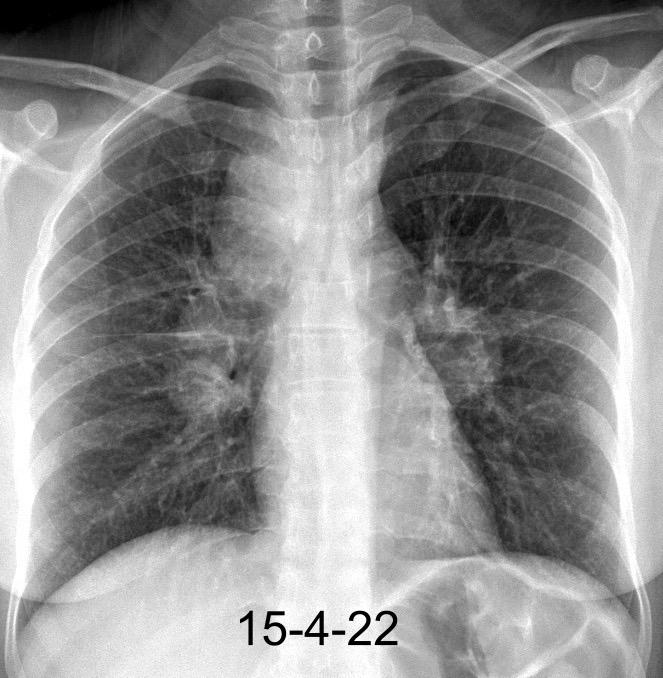

Carcinoma microcítico con síndrome de VCS

Síntomas y signos que se producen con la obstrucción total o parcial de la vena cava superior

Causas Malignas +/- 90-95%

Ca. Broncogénico (80-85%)

Linfoma No Hodgkin (15%)

Catéteres, shunts y marcapasos…23%

T. Mediastínico. Bocio

Fibrosis Idiopática

Tb, Histoplasmosis, Actinomicosis, Sarcoidosis